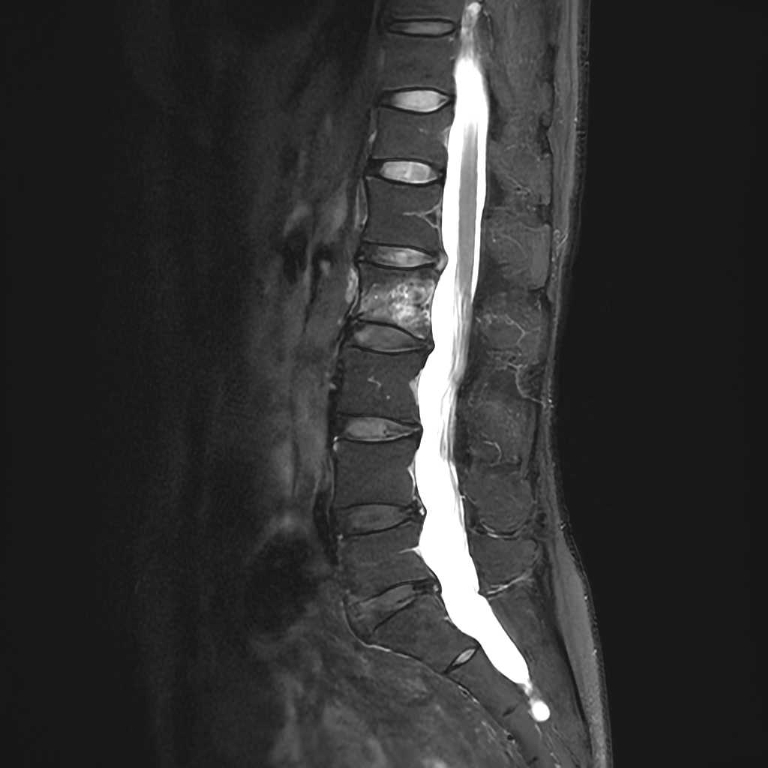

MRI検査

整形外科領域

脊椎

椎間板ヘルニア

圧迫骨折